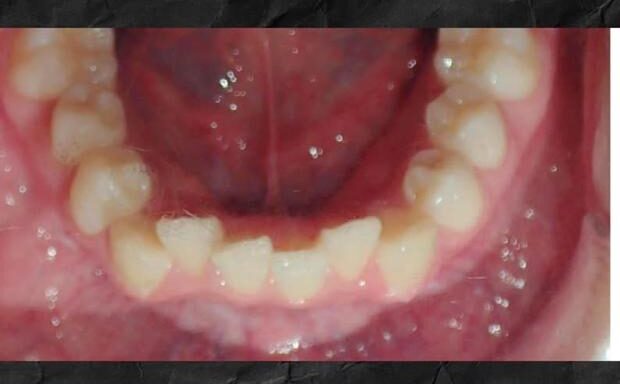

Lower severe crowding

Lower front teeth tend to respond very well to orthodontic treatment using invisalign